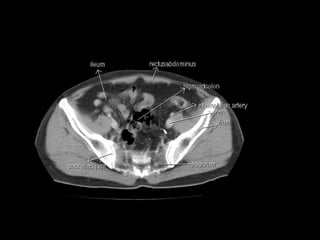

Radiographers use medical imaging equipment like X-rays and MRIs to produce images of patients' internal structures and organs. They are responsible for positioning patients, operating scanning machines, and ensuring quality images. Radiographers must have strong attention to detail, excellent communication skills, and the ability to work well under pressure to accurately capture anatomical features and diagnose any abnormalities.